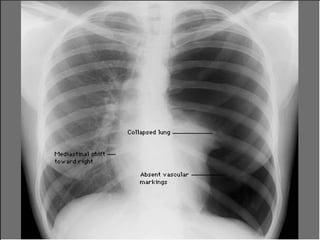

PNEUMOTHORAX

Aortic dissection with hemothorax

Left Sided Pneumothorax